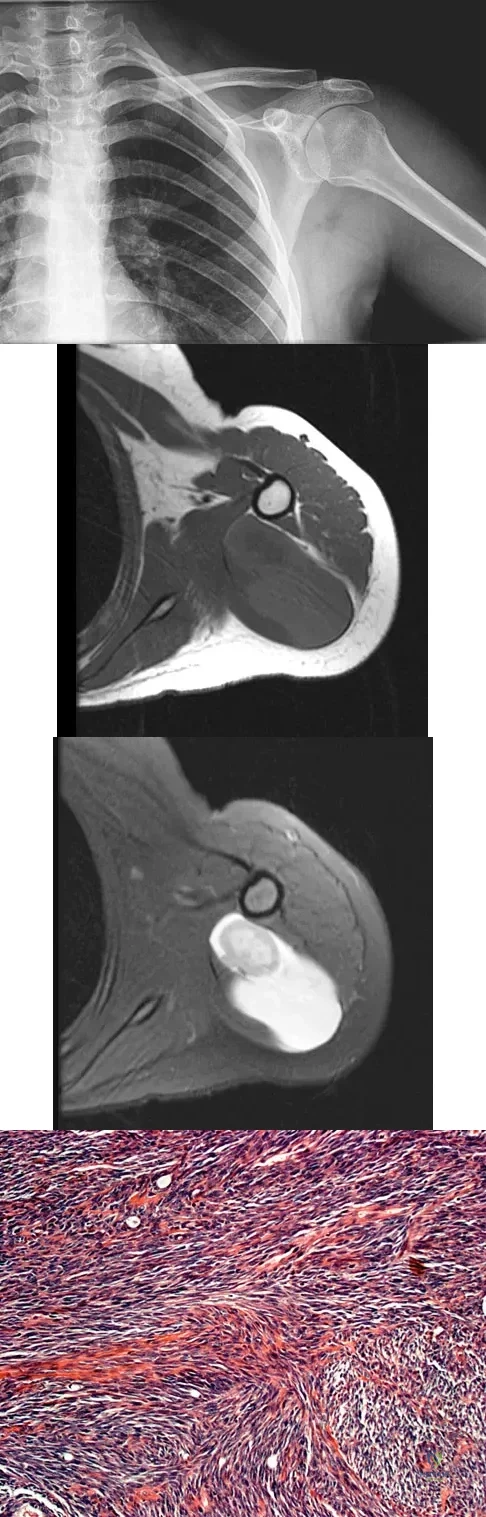

A 37-year-old man pulled his hamstring playing softball 3 weeks ago. The patient had not noted any mass prior to his injury. MRI scans of the posterior thigh are shown in Figures 4a and 4b. Figure 4c shows the biopsy specimen from a needle biopsy. What is the most likely diagnosis?

Explanation